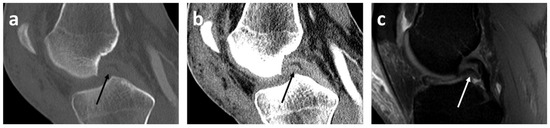

- Presence or absence (yes/no) of mentioned radiological signs of dislocated bucket handle meniscal tears (double delta sign, disproportional posterior horn sign, double PCL sign)